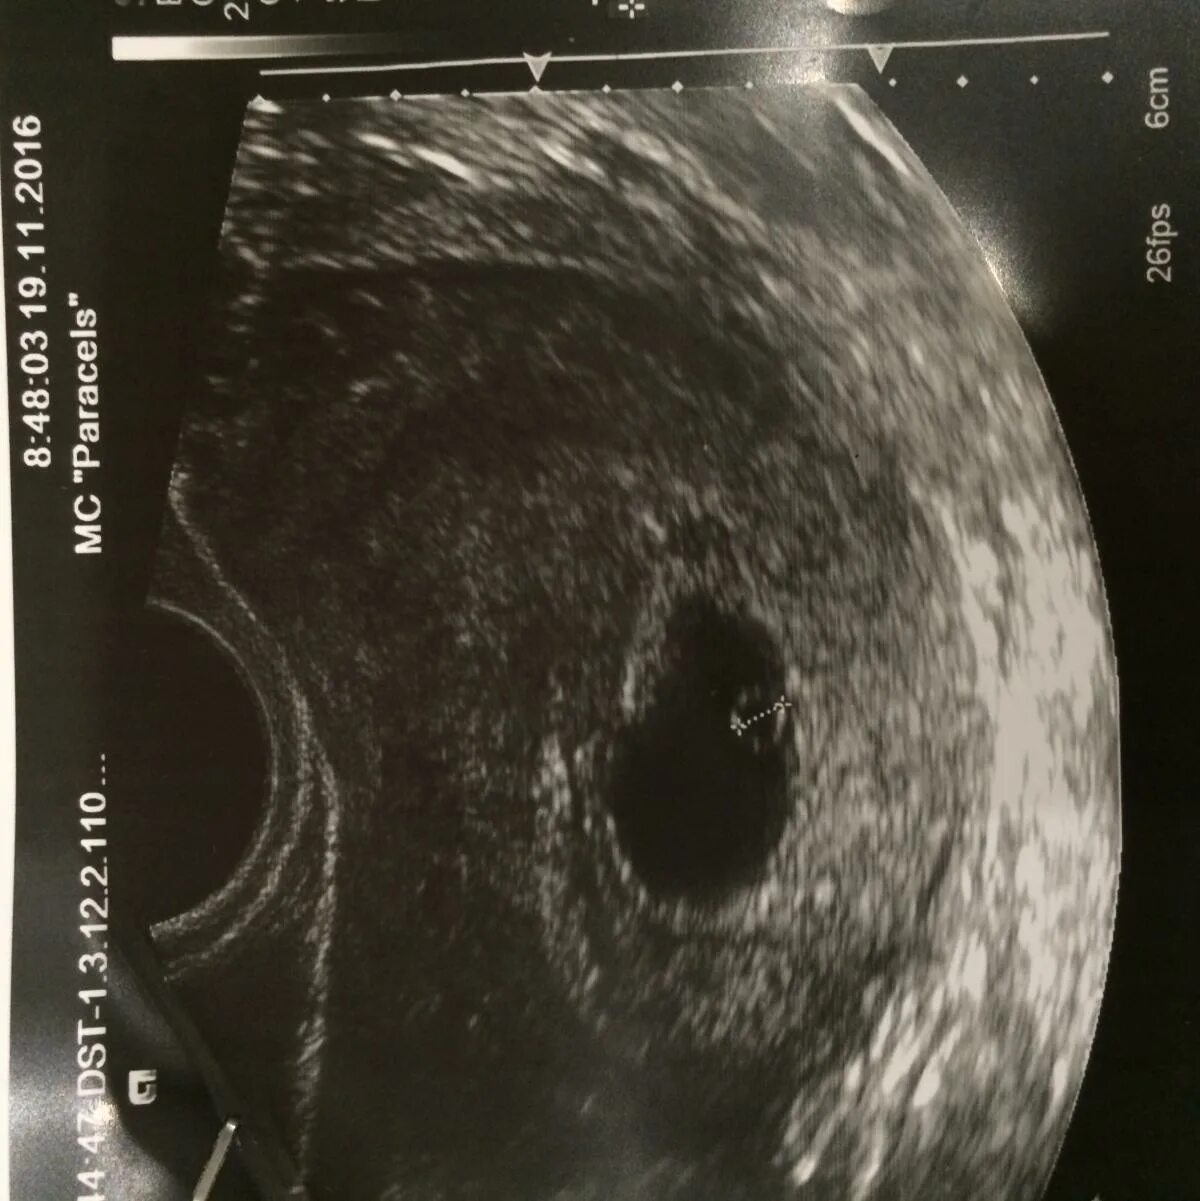

Желточный мешок 2 мм